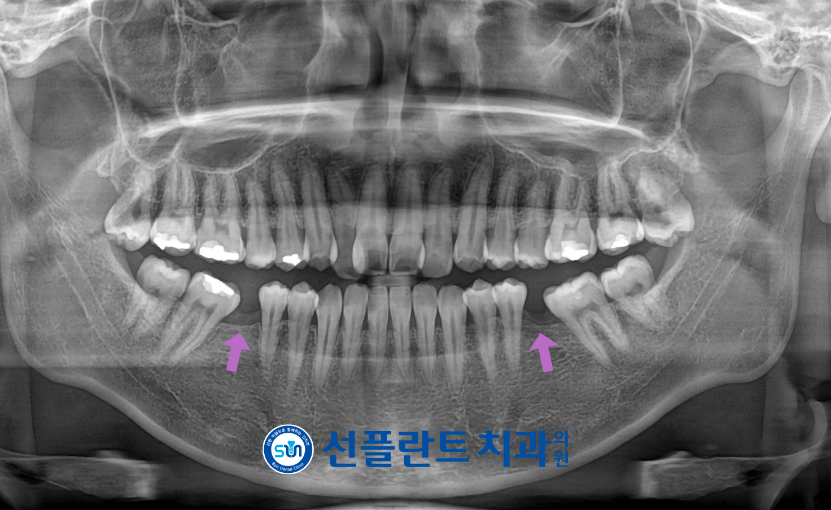

오늘은 아래턱 양측 어금니 결손과

위턱 앞니의 덧니로 인해

용인선플란트치과를 내원해 주신

환자분의 사례를 소개해 드리겠습니다.

환자분께서는 20대 남성분으로

아래턱 양측 첫 번째 큰 어금니 상실로 인한

수복치료와

위턱 앞니 덧니로 교정치료를 원하신다고

말씀해 주셨는데요.

먼저 구강 내를

확인해 보았더니

아래턱 양측 첫 번째 큰 어금니의 상실로

바로 옆의 두 번째 큰 어금니가

앞쪽으로 기울어져

위아래 교합 불균형이 확인되었으며,

위턱 앞니도 공간 부족으로 인해

덧니 및 배열 불량이 동반된 상태였습니다.

정밀한 검사를 위해

파노라마 사진을 촬영해 보았습니다.

상실된 아래턱 양측 첫 번째 큰 어금니(#36,46)에

임플란트 수복을 하기에는

기울어진 두 번째 큰 어금니(#37,47)로 인해

공간 부족으로 바로 식립이 어려운 상태였는데요.